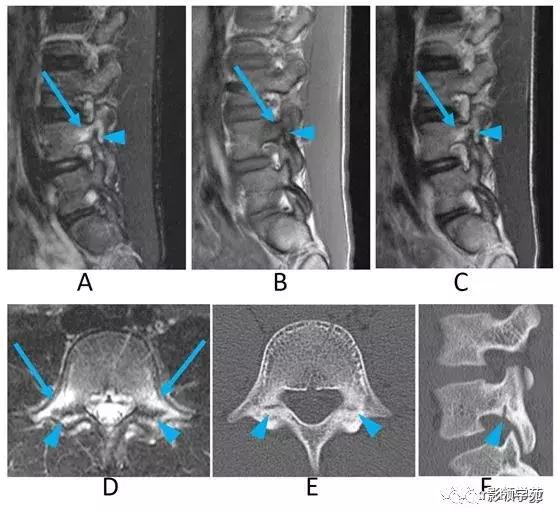

图9:早期椎弓峡部裂。男,10多岁。

A:STIR矢状位图像,

B:T1WI矢状位图像,

C:T2WI矢状位图像,

D:STIR斜向轴位图像,

E:平面CT斜向轴位图像,

F:CT平面矢状位重组图像。

MRI图示,L4双侧椎弓和关节突在T1WI像上呈低信号,T2WI像呈高信号(B,C箭)的信号强度较高。STIR更清楚地显示骨髓高A,D箭)。

CT图示裂隙位于的关节突下部(E,F箭头),MRI图像上显示为低信号(A-D箭头)。